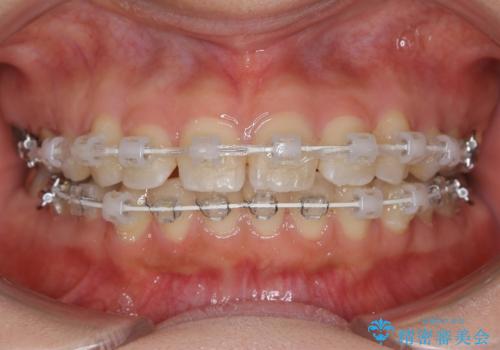

前歯のガタつきを改善 抜歯矯正後の後戻り

- 矯正装置

- 審美装置

- 抜歯矯正後の後戻りで前歯ガタつきが主訴で来院された患者様です。

後戻り矯正や非抜歯矯正はインビザラインをご案内する事が多いですが、自己管理の煩わしさから、目立たないワイヤー装置にて矯正治療を行うこととしました。

後戻りの程度としては軽度なので、治療期間としては短く終えることが出来ました。

前歯の正中線も改善され大変満足して頂きました。